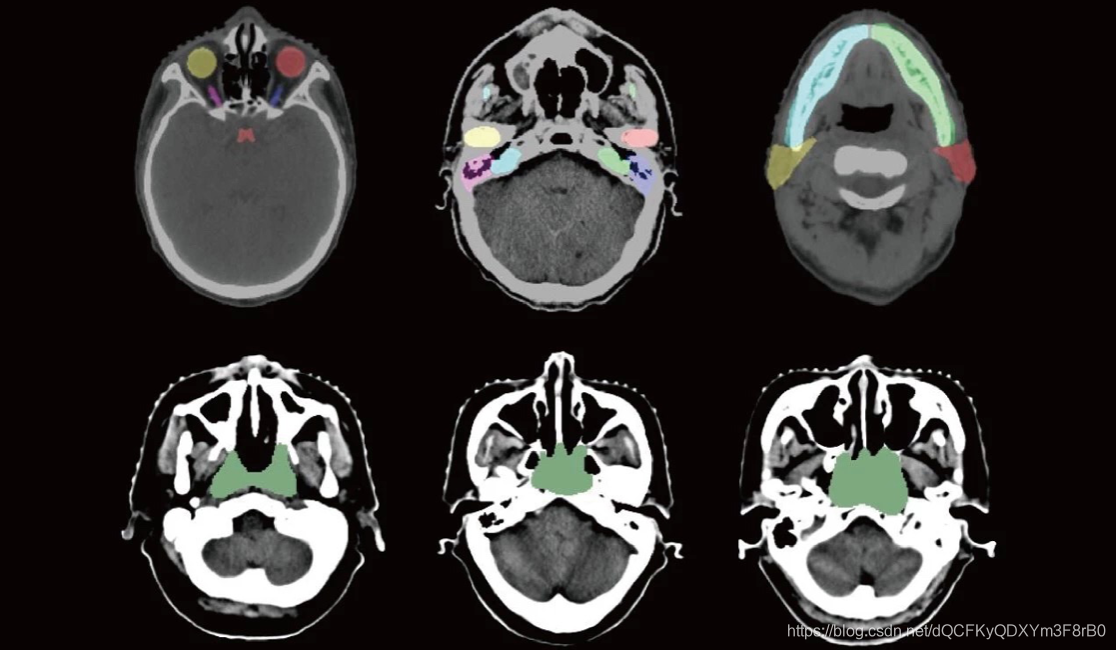

但业内普遍缺乏标准化高质量的训练数据,此次主办的MICCAI 2019放疗规划自动结构勾画国际挑战赛,将公布大量具有专家标注的CT数据,用于此次“头颈部危及器官(OAR)分割”、“胸部危及器官(OAR)分割”、“鼻咽癌放疗靶区(GTV)分割”和“肺癌放疗靶区(GTV)分割”四项挑战任务。这些CT数据包含鼻咽癌与肺癌两种癌症数据,且本次数据集规模比以往所有公开数据集规模都大,包含了50位鼻咽癌患者的CT数据及相应的1100个危及器官和放疗靶区GTV的标注,50位肺癌患者的CT数据及相应的300个危及器官和放疗靶区GTV的标注,这些数据集的释放,将极大地推动CT图像中危及器官和靶区勾画研究的进展。